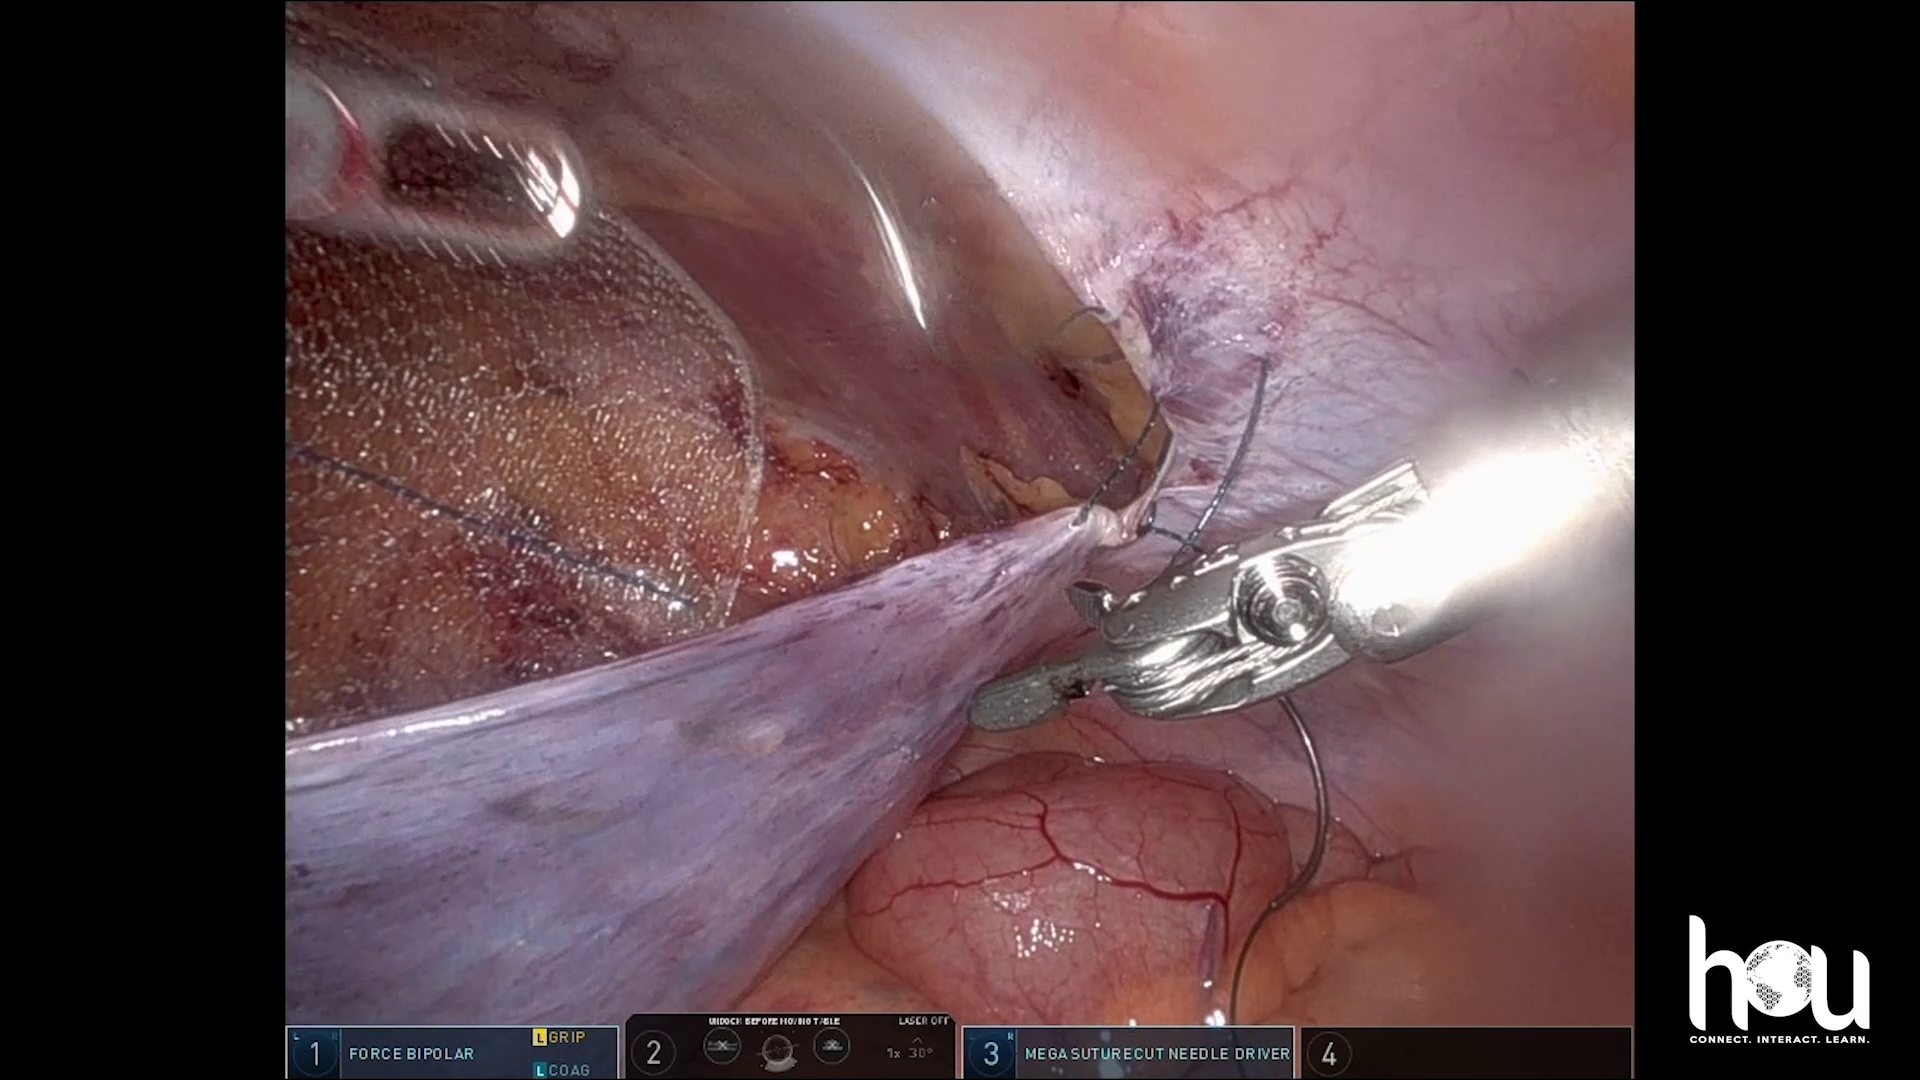

Dr. Malcher | R TAPP abs

Robotic repair of inguinal scrotal hernia with abadoned the sac technique